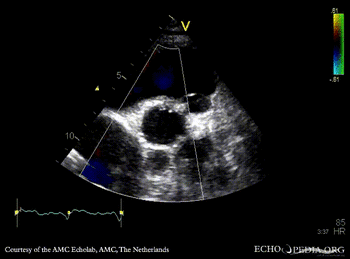

Abscess of aortic valve prosthesis

PLAX: Abscess of aortic valve prosthesis PLAX with Color Doppler